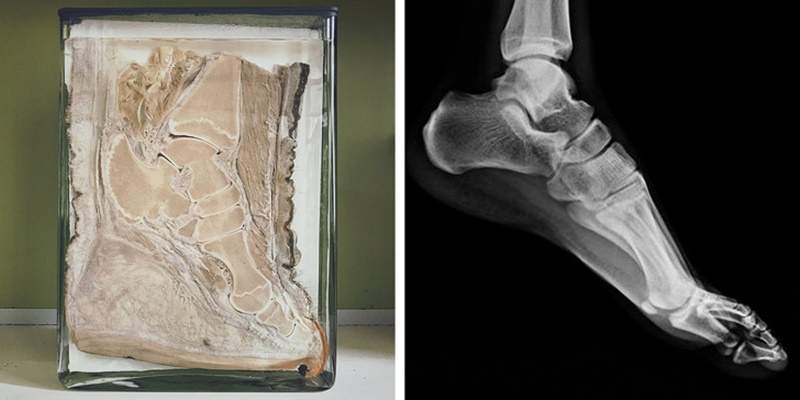

大象腳骨頭跟人類骨型很像

圖片來自:https://brightside.me